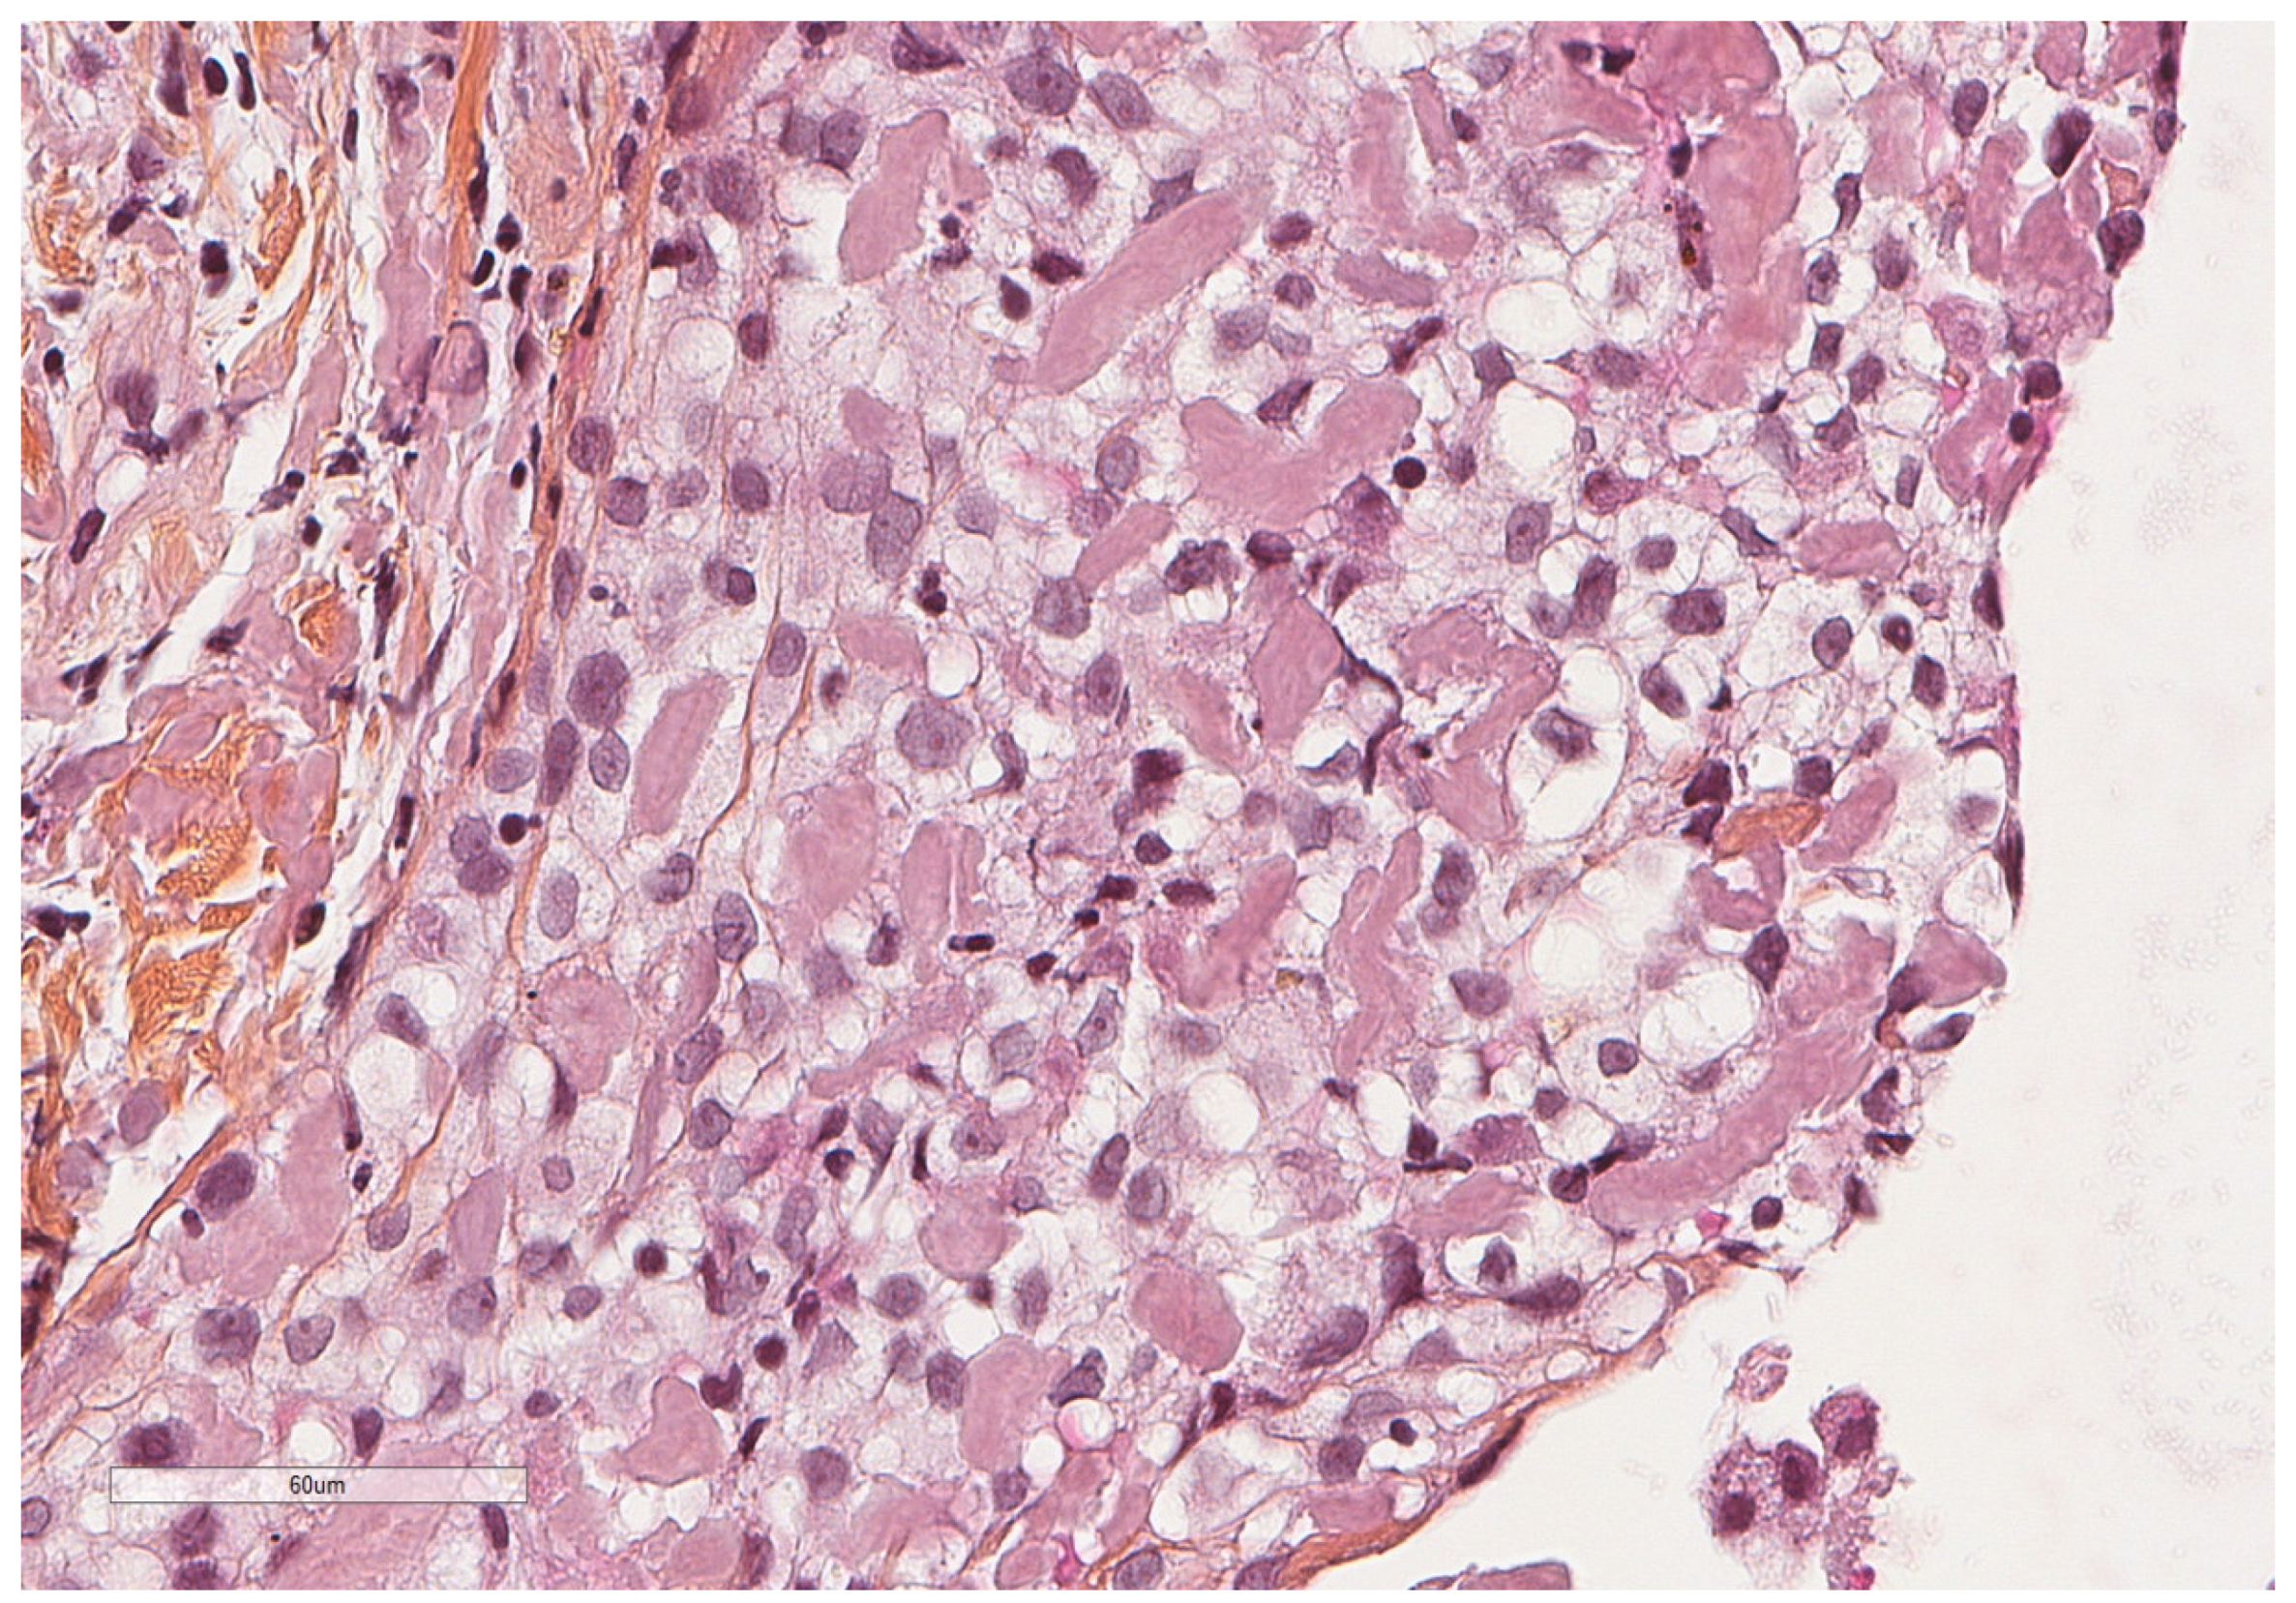

- Karpathiou, G.; Hathroubi, S.; Patoir, A.; Tiffet, O.; Casteillo, F.; Brun, C.; Forest, F.; Rahman, N.M.; Peoc’h, M.; Froudarakis, M.E. Non-specific pleuritis: Pathological patterns in benign pleuritis. Pathology 2019, 51, 405–411. [Google Scholar] [CrossRef] [PubMed]